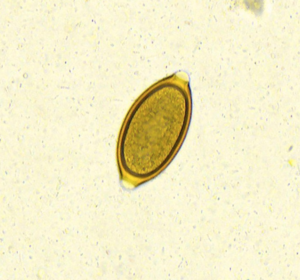

Peitschenwürmer

Befallen: Hunde (selten Katzen)

Mögliche Symptome: Gewichtsverlust, Durchfall